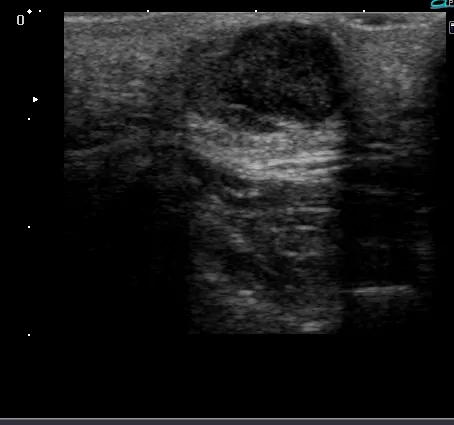

超音波検査では内部が低エコーで後方エコーが増強、腫瘍に血管の進入はありません(超音波検査)。

超音波検査